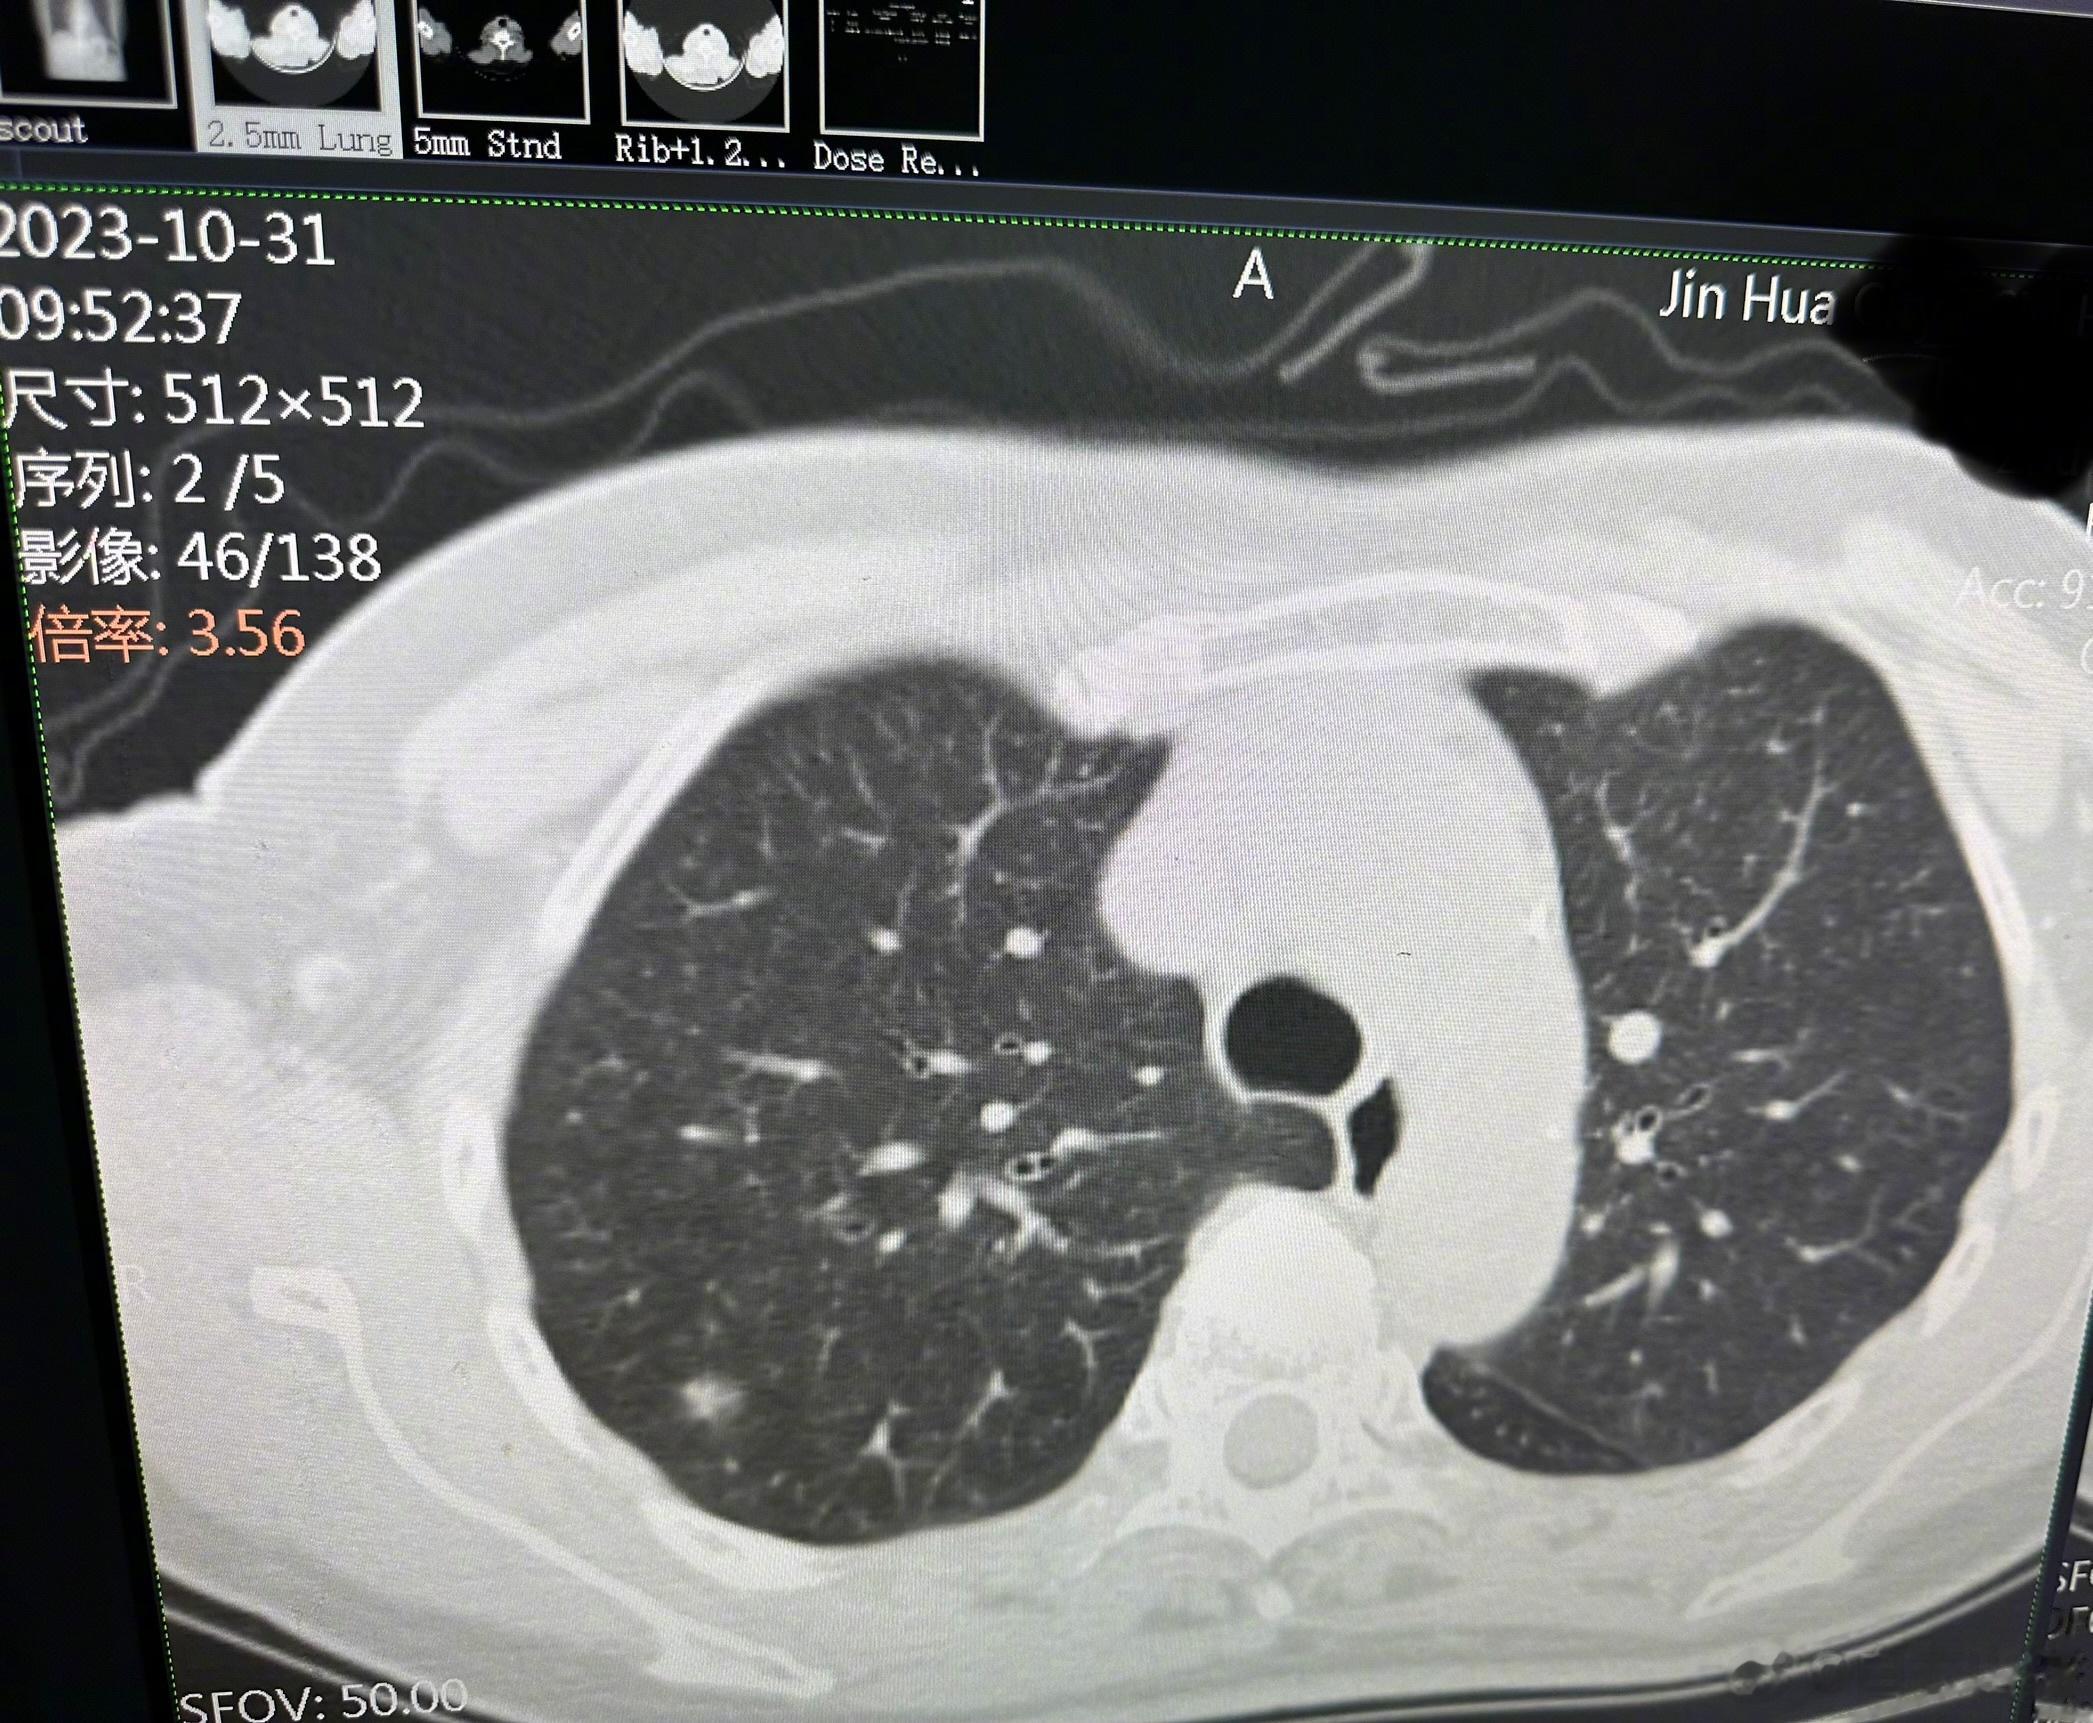

在2021年初,她在体检的时候发现了肺结节,毛玻璃样,右肺上叶两个、右肺下叶一个,左肺上叶一个。此后每六到八个月,复查一次肺部CT,一直到今年的两月份,肺结节都没有明显的变化。

但是我看到今天的CT上,右肺上叶有一个结节(图2),和今年两月份的片子(图1)比起来,虽然没有明显增大,但是密度明显增高了,也就是说,这个结节内,有实性的组织在生长。这就是一个手术指征了。